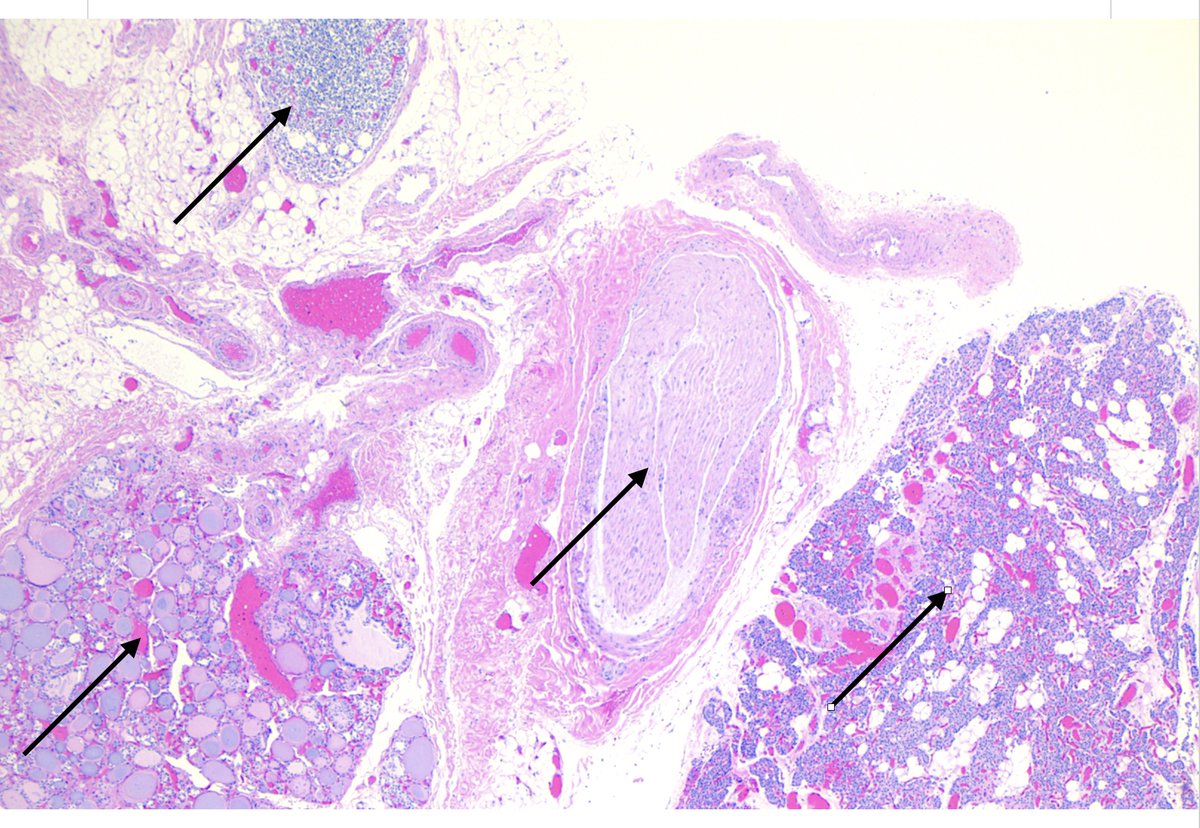

#MTPathUnknown #273

For medical students

Histology review--what are the four things at the arrows.

I just thought this was a neat image with the four different tissues in the same low power field.